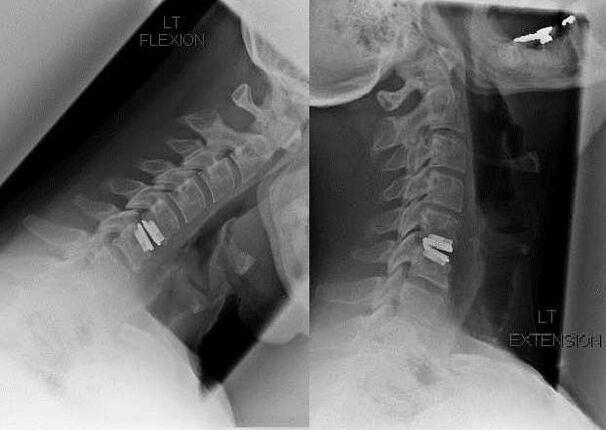

Las indicaciones para la intervención quirúrgica incluyen la ineficacia del tratamiento conservador, así como las complicaciones de la osteocondrosis cervical, por ejemplo, mielopatía discogénica, síndrome de la arteria vertebral y síndrome radicular. Para descomprimir la médula espinal, los vasos sanguíneos y las raíces espinales se realizan las siguientes operaciones:

- laminectomía;

- laminotomía;

- foraminotomía;

- facetectomía;

- discectomía.

Durante la cirugía, se pueden extirpar fragmentos óseos y ligamentos y se pueden extirpar total o parcialmente los discos intervertebrales. Para pequeñas protuberancias herniarias, a menudo se realiza la vaporización con láser del núcleo del disco.

Después de la escisión de las estructuras vertebrales, a menudo se requiere la estabilización de los segmentos de movimiento de la columna mediante fusión espinal o instalación de autoinjertos óseos y dérmicos.